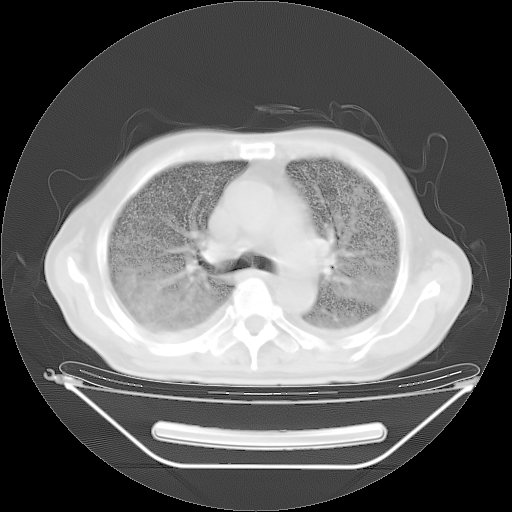

今天复查肺部CT,发现双肺广泛磨玻璃样改变。所以我把3月19日和5月9日相隔50天的肺部CT上传。请大家会诊。

2009年3月19日肺部CT片。

5月9日肺部CT(在4月27日齐鲁医院肺部CT描述部分肺组织磨玻璃样改变,12天后肺组织广泛磨玻璃样改变)

大致读了系列胸部CT:纵隔窗无明显异常,肺窗:从4、27至今:主要是双肺中下野外带可见毛玻璃样改变,目前处于急性肺泡炎阶段,至于原因考虑1、结替组织或胶原血管性疾病所致?2、恶性疾病如恶组在肺部所致的表现或细支气管肺泡癌?3、药物或其它原因如肺蛋白沉着症所致肺泡炎目前不太可能?总之,明天就去请我院的呼吸科、感染科、血液科和临免专家会诊哈。